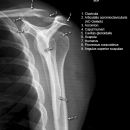

Schulter seitlich (Y-View)

Bei Luxation zusätzlich zur glenoidtangentialen Aufnahme problemlos durchführbar! Axiale Aufnahme schmerzbedingt meist nicht möglich.

- Skapula bildet sich als Y ab

- Humeruskopf projiziert sich in das Glenoid? Luxation? Luxationsrichtung?

- Weite des subacromialen Raumes exakt nur in der 10 – 15° nach kaudal angulierten Aufnahme bestimmbar („Morrison, Outlet View“)! Normalerweise 1 - 1,5 cm, < 6 mm -> wohl pathologisch, Impingment wahrscheinlich

- Normvarianten: Os glenoidale (akzessorischer Ossikel kaudal des Glenoids), persistierende Akromion- oder Korakoidapophyse, entwicklungsbedingte Pfannenranddefekte

- Schulterluxationen:

- Anteriore Luxation (2) 95%= anteriore infraglenoidale Luxation, Kopf liegt vor Glenoid

- Posteriore Luxation (2) 3%: wird häufig übersehen! Kopf liegt hinter Glenoid, Hochstand des Humeruskopfes, fixierte Innenrotation des Humeruskopfes => atypische Projektion des Humeruskopfes: “ drumstick or bulb appearance“ (Birnenform), Muldenzeichen („trough line“), „rim sign“ in der ap bzw. glenoidtagentialen Aufnahme.

Zweite Ebene, z.B. transskapuläre Aufnahme zeigt die Richtung der Luxation. Cave. rein klinische Diagnose!

- Begleitverletzungen? (-> heute umfassend mit CT/MRT zu beurteilen)

- Tuberculum majus (15%)

- Pfannenrand

- Hill- Sachs Läsion = Dorsokraniale Humeruskopf-Impressionsfraktur (50%) (Aufnahme der 1. Wahl: Stryker oder CT)

- umgekehrte Hill-Sachs Läsion = anteromediale Impression nach hinterer Luxation

- Bankart-Läsion: Abriss des vorderen Labrum-Kapsel-Komplexes bzw. Abrissfraktur des vorderen unteren Glenoidrandes (-> CT-Athrographie, Arthro-MRT)